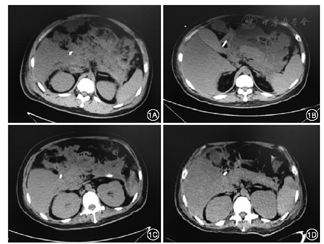

2016年1月15日在CT引导下行胰周脓肿经皮穿刺引流术,置入长25 cm、直径16 F单猪尾引流管2根,穿刺液培养为铜绿假单胞菌。此后患者体温稍下降,1个月后患者再次出现高热,伴有血压下降,联合使用去甲肾上腺素、多巴胺等血管活性药物维持血压。复查血常规示白细胞计数19.7×109/L、中性粒细胞百分比89.8%,血清降钙素原20.94 μg/L;腹部CT检查提示胰周仍有大范围脓肿(图1)。经胰腺外科等多学科会诊认为患者目前肾功能衰竭尚未恢复,且伴有感染性休克,手术风险高,建议行内镜下治疗。遂于2016年2月25日在内镜引导下行经皮内镜胰周脓肿清除术。气管插管麻醉成功后,患者仰卧位,取原腹部左侧引流管窦道,使用经皮肾镜皮肤扩张器将窦道口扩至1 cm,置入直径12 mm Trocar,置入电子胃镜,可见腹膜后大量坏死组织及脓液(图2),用网篮及三爪钳清除坏死组织,术毕置入双套管引流。此后患者体温仍有波动,于2016年3月8日及17日再次行经皮内镜胰周脓肿清除术,经治疗后患者体温恢复正常,复查降钙素原为0.747 μg/L,CT检查提示胰周脓腔基本消失。此后患者尿量逐渐增加,至2周后尿量>2 000 ml/d,先后拔除腹腔引流管、血液滤过置管和空肠营养管,于2016年5月12日痊愈出院。